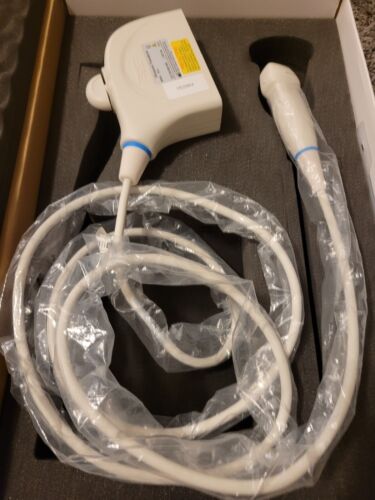

Mindray M5 Portable Ultrasound With New Linear Vascular/MSK Probe, Case

Regular price $4,599.00 USDRegular priceUnit price / per -